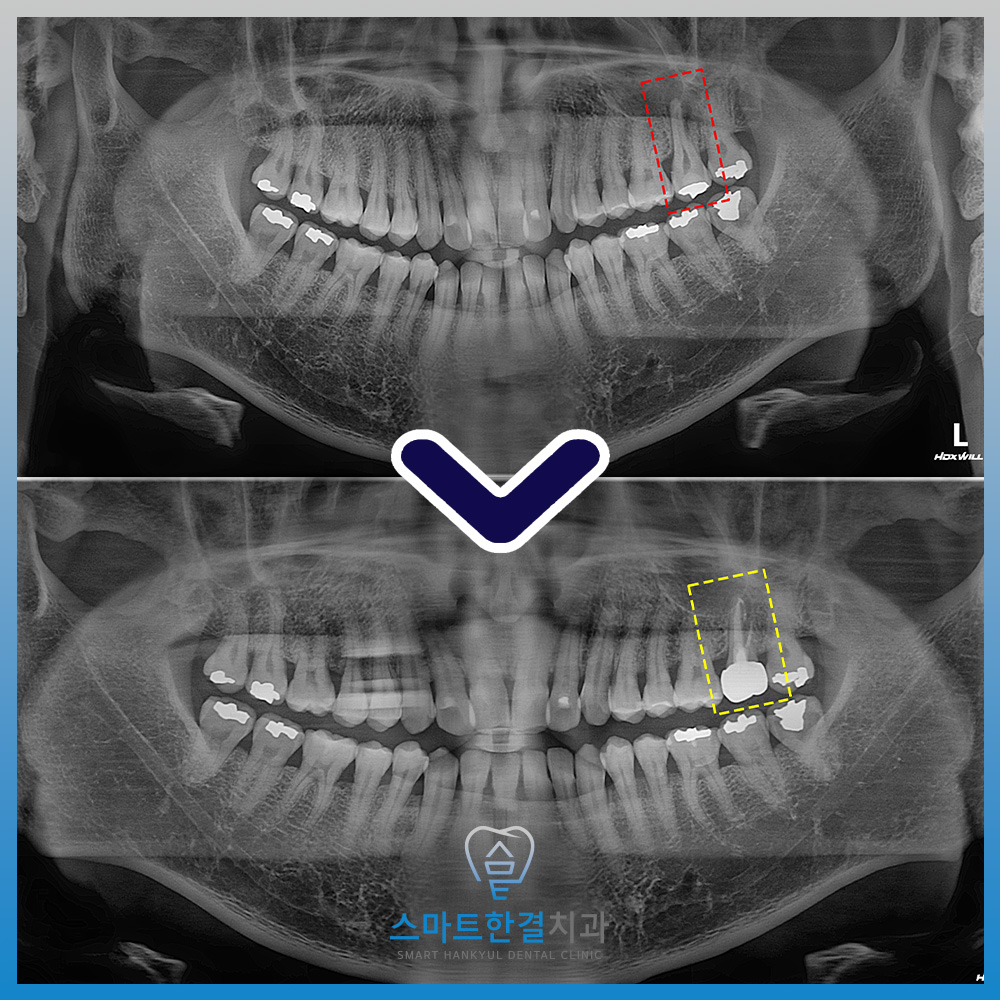

신경치료 이후 뿌리 끝 염증이

점차 완화되는 것을 확인할 수 있었으며

잇몸에 형성되어 있던 누공 또한

점차 사라지는 양상을 보였는데요.

이에 기능적으로 약해진 치아를 보호하고

재파절을 예방하기 위해

최종적으로 크라운 치료를 진행하였으며,

현재는 통증 없이 안정적으로

일상적인 저작이 가능한

상태를 유지하고 있답니다.^^

화서동치과 스마트한결치과의

신경치료 전후 사진이에요.